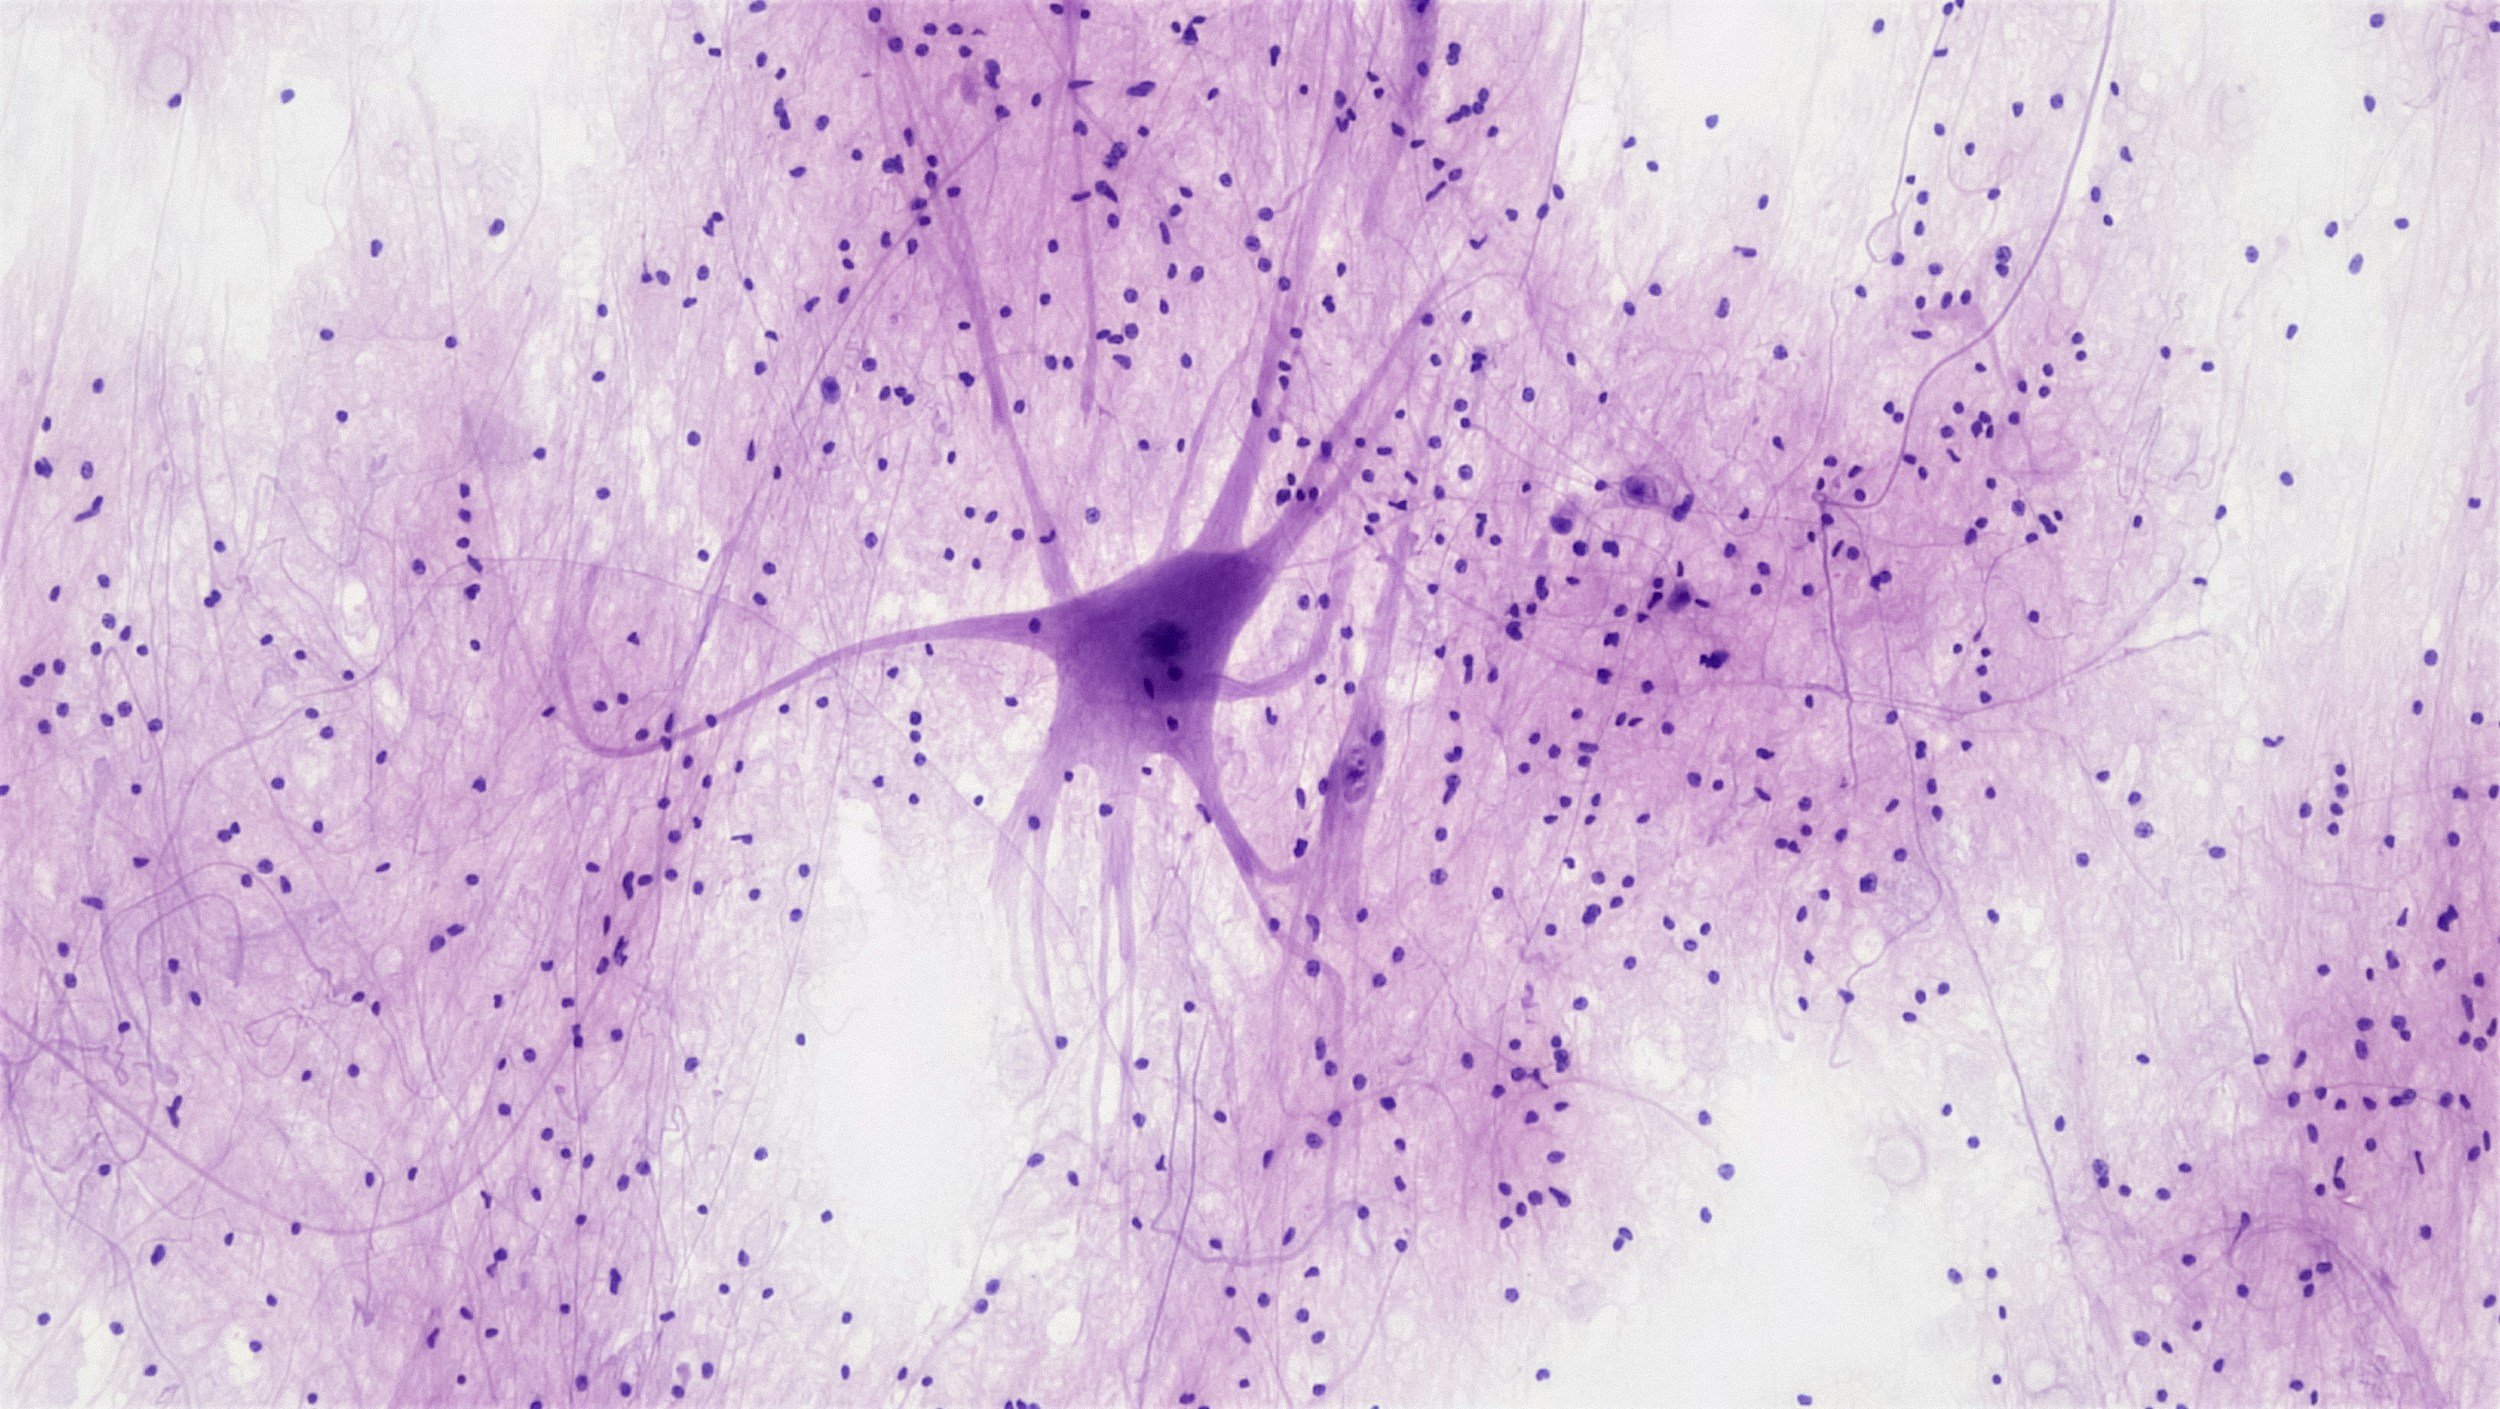

Can Neuroscience Explain What Makes Fatigue Chronic?

The new science of predictive processing is prompting researchers to understand fatigue in a new way. Persistent fatigue may be the result of the brain's hyper-vigilance following multiple stressors. Positively, we can harness the brain's neuroplasticity to nudge it to become more flexible in its outlook.

ME/CFS and long Covid: Your Brain May Be Trying to Protect You

If you are living with ME/CFS and long COVID, you may be asking: Why has my body gone into shutdown mode? A viral infection or another trigger may act as the final straw after cumulative stresses. The brain may then conclude that the body is unable to meet the challenges facing it. The brain may revert to a hyper-protective state. This may cause a lasting "sickness response" in the body.